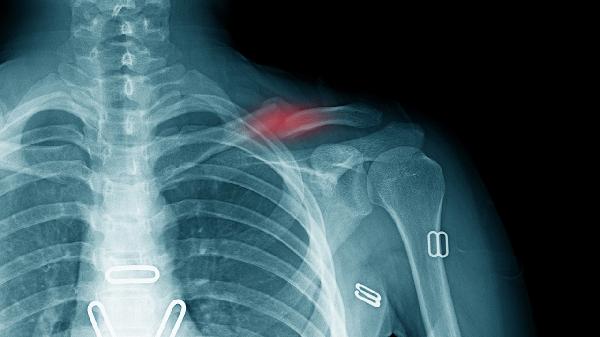

胸椎骨折后一般会疼多久?

胸椎骨折后疼痛一般持续4-8周,实际恢复时间与骨折严重程度、治疗方式、年龄、康复训练及并发症等因素有关。

轻度压缩性骨折疼痛约2-4周,椎体高度丢失小于20%时,疼痛主要来源于局部软组织损伤。中度骨折伴随30%椎体高度丢失时,疼痛可持续6周,需配合支具固定。重度爆裂性骨折疼痛可能超过8周,多伴有神经压迫症状。